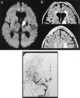

Idiopathic multiple arterial stenoses